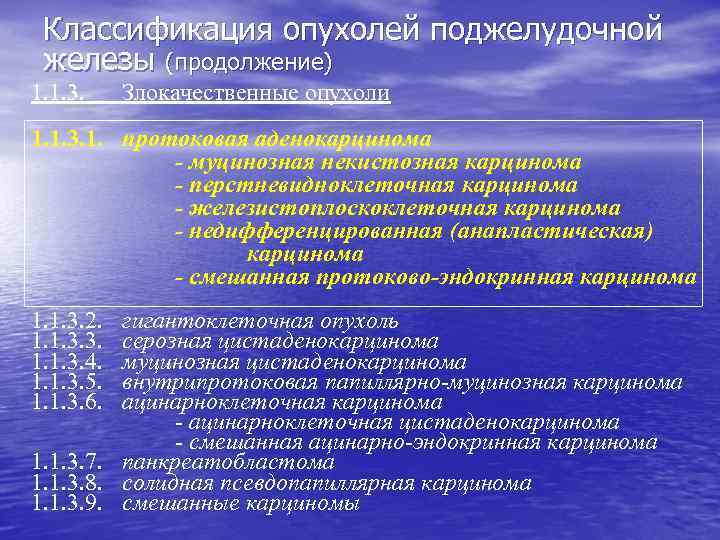

Классификация опухолей поджелудочной железы (продолжение) 1. 1. 3. Злокачественные опухоли 1. 1. 3. 1. протоковая аденокарцинома - муцинозная некистозная карцинома - перстневидноклеточная карцинома - железистоплоскоклеточная карцинома - недифференцированная (анапластическая) карцинома - смешанная протоково-эндокринная карцинома 1. 1. 3. 2. 1. 1. 3. 3. 1. 1. 3. 4. 1. 1. 3. 5. 1. 1. 3. 6. гигантоклеточная опухоль серозная цистаденокарцинома муцинозная цистаденокарцинома внутрипротоковая папиллярно-муцинозная карцинома ацинарноклеточная карцинома - ацинарноклеточная цистаденокарцинома - смешанная ацинарно-эндокринная карцинома 1. 1. 3. 7. панкреатобластома 1. 1. 3. 8. солидная псевдопапиллярная карцинома 1. 1. 3. 9. смешанные карциномы